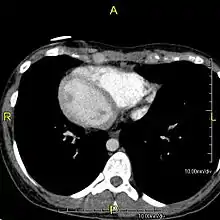

However, in some individuals with PCD, mutations thought to be in the gene coding for the key structural protein left-right dynein (lrd)[8] result in monocilia which do not rotate. There is therefore no flow generated in the node, Shh moves at random within it, and 50% of those affected develop situs inversus, which can occur with or without dextrocardia, where the laterality of the internal organs is the mirror-image of normal. Affected individuals therefore have Kartagener syndrome. This is not the case with some PCD-related genetic mutations: at least 6% of the PCD population have a condition called situs ambiguus or heterotaxy, where organ placement or development is neither typical (situs solitus) nor totally reversed (situs inversus totalis) but is a hybrid of the two. Splenic abnormalities such as polysplenia, asplenia and complex congenital heart defects are more common in individuals with situs ambiguus and PCD, as they are in all individuals with situs ambiguus.[14]

When accompanied by the combination of situs inversus (reversal of the internal organs), chronic sinusitis, and bronchiectasis, it is known as Kartagener syndrome[1] (only 50% of primary ciliary dyskinesia cases include situs inversus).